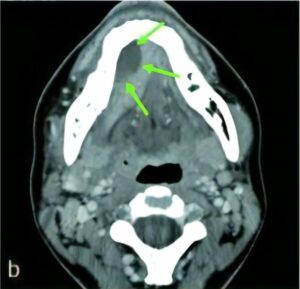

炎症

歯周病やう蝕から細菌感染が、顎の骨や周囲の軟組織、リンパ節、上顎洞などにおよぶことがあります。

膿が貯まっている場合、切開し膿を出したり、抗菌薬を投与し治療します。

しかしながら、治療の基本は、十分な安静や栄養摂取ですので、家庭の環境により安静にしていられない方や、腫れや痛みで栄養が十分摂取できない場合や重度の炎症の場合には、入院治療が必要な場合があります。